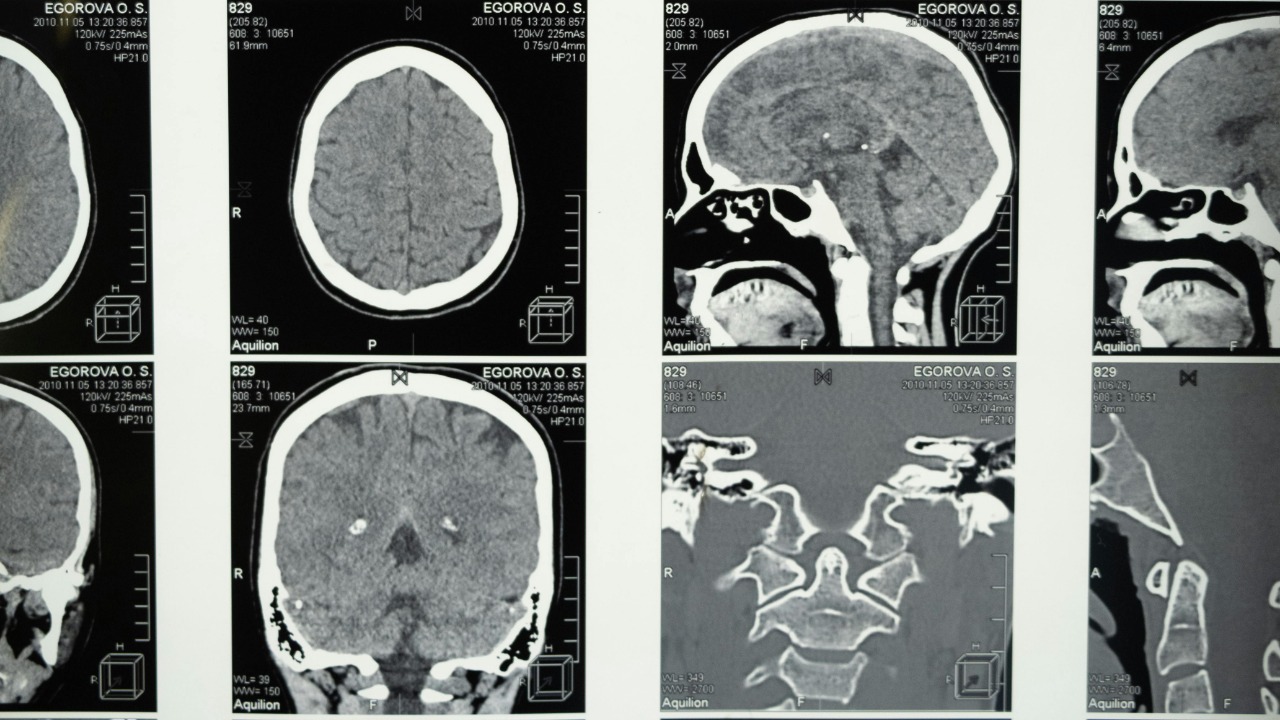

Brain tumor Brain tumor

Glioblastoma is the kind of diagnosis that redraws a life in an instant, a brain cancer so aggressive that survival is usually measured in months and not years. For decades, surgery, radiation and chemotherapy have barely nudged the statistics, and there is still no approved cure. Now, a series of converging advances is giving researchers something they have rarely had in this field: a plausible kill switch that might shut down the disease at its molecular core.